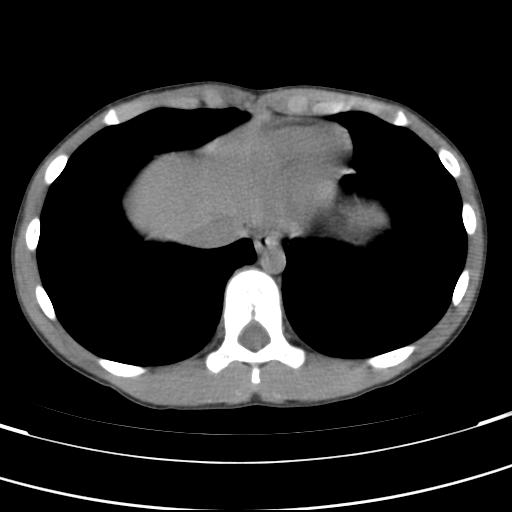

标题: PED3157:左肾缺如,请教脾脏的改变?、、

男孩,9岁。胃部不适。

脾脏位于左侧,但数个脾脏呈分离状态,左肾缺如,右肾代偿肥大。考虑多脾综合征。